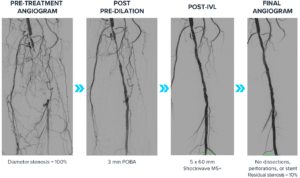

A 72-year-old female patient presented with lifestyle-limiting claudication and rest pain at night with worse symptoms in the left leg. The patient is a former smoker, has diabetes, CTO and chronic kidney disease (CKD). Invasive angiography of the left leg showed a chronic total occlusion in the P1 and P2 segments of the popliteal with no iliac disease and three vessel runoff to the feet. The CTO was crossed and a 3.0 mm POBA was used for the initial dilation. Then a 5.0 mm Shockwave M5+ was used along the calcified segments, finishing with a drug-coated balloon (DCB). Intravascular ultrasound (IVUS) imaging of calcified segments showed no dissections and good vessel expansion.